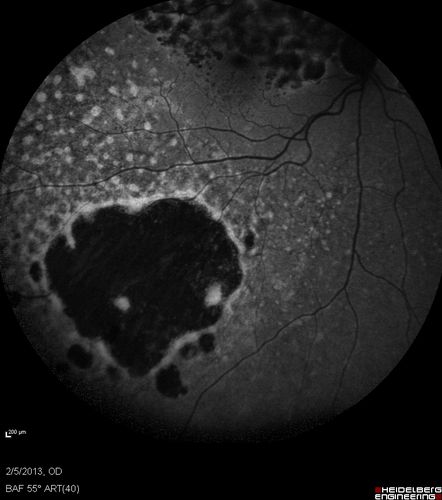

Primary Ocular Lymphoma - 020513 - FUndus Autofluorescence

Primary Ocular Lymphoma